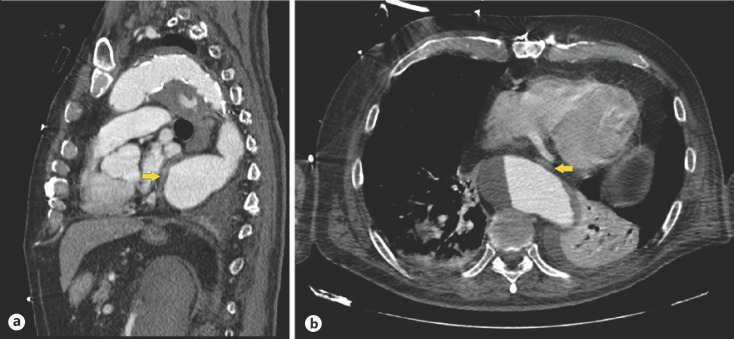

Dysphagia Aortica: An Uncommon and Potentially Life-Threatening Condition.

大动脉吞咽困难:一种不常见且可能危及生命的疾病。